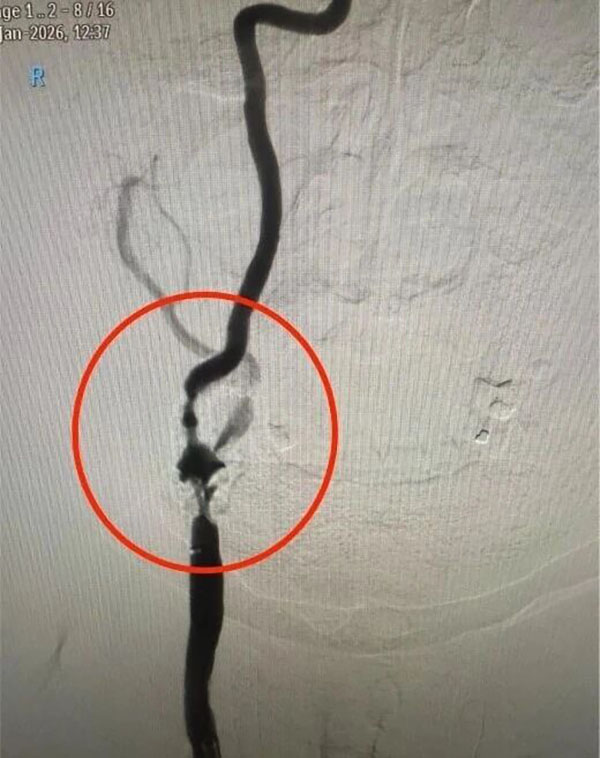

上图为该患者手术前重度狭窄的血管

传统药物保守治疗难以从根本上解决血管狭窄问题,无法有效规避脑梗死的风险。面对这一棘手局面,血管介入科马心龙副主任决定组织一场疑难病例讨论,同时邀请呼吸科、心内科、重症医学科等专家开展多学科会诊,全面评估患者的身体状况、血管条件及手术耐受性。同时,反复推演手术流程,细致排查术中可能出现的血压骤变、心律失常、斑块脱落、脑血管痉挛等风险点,并制定了针对性的应急处理方案。

在与患者家属充分沟通手术的高风险性及预期效果后,获得家属理解与手术意愿,医护团队决定为患者实施微创颈内动脉支架植入术。为保障手术安全,术前医护团队为患者优化基础疾病控制方案,精准调整血压、心率及凝血功能,做好各项术前准备工作。介入导管室提前调试数字减影血管造影(DSA)设备,备好远端保护装置、适配球囊、自膨式支架等精密器械确保手术高效开展。

手术过程中,血管介入科团队以毫米级精度开展穿刺、置鞘、导引导管到位等步骤,精准地将微导丝穿过狭窄血管段,随后放置远端保护装置,如同为大脑血管筑牢“安全屏障”,有效预防术中斑块脱落引发栓塞。紧接着,选用合适规格的预扩张球囊对狭窄部位进行轻柔扩张,为支架植入开辟通路,随后将一枚自膨式支架精准送达狭窄段,缓慢释放并确认支架完全展开、贴壁良好。整个手术历时约60分钟,患者术后造影显示,患者颈内动脉狭窄部位血流完全恢复通畅,无残余狭窄,手术达到了团队预期的效果。